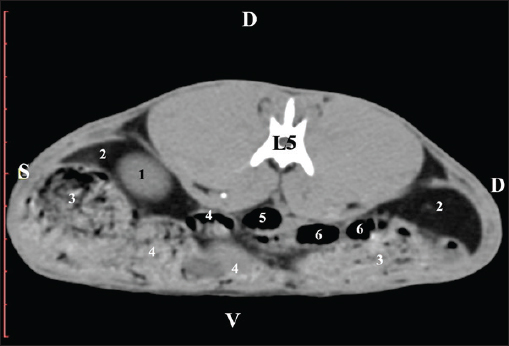

The L5 scan revealed the caudal end of the left kidney. It was adjacent to some small intestinal segments, including the duodenal pars ascendens, ileum, cecum, and colon ascendens (Figs. 12 and 13).

Fig. 12. Pre-contrast computed tomography (CT) anatomical scan of the regio-abdominis media at the cranial L5 edge level. (1) Ren sinister; (2) adipose collections; (3) cecum; (4) colon ascendens; (5) jejunum; (6) pars ascendens of the duodenum; (7) colon transversum; (8) colon descendens.

Fig. 13. Pre-contrast computed tomography (CT) anatomical scan of the regio-abdominis media at the caudal L5 edge level. (1) Ren sinister; (2) adipose collections; (3) cecum; (4) colon ascendens; (5) colon transversum; (6) colon descendens.